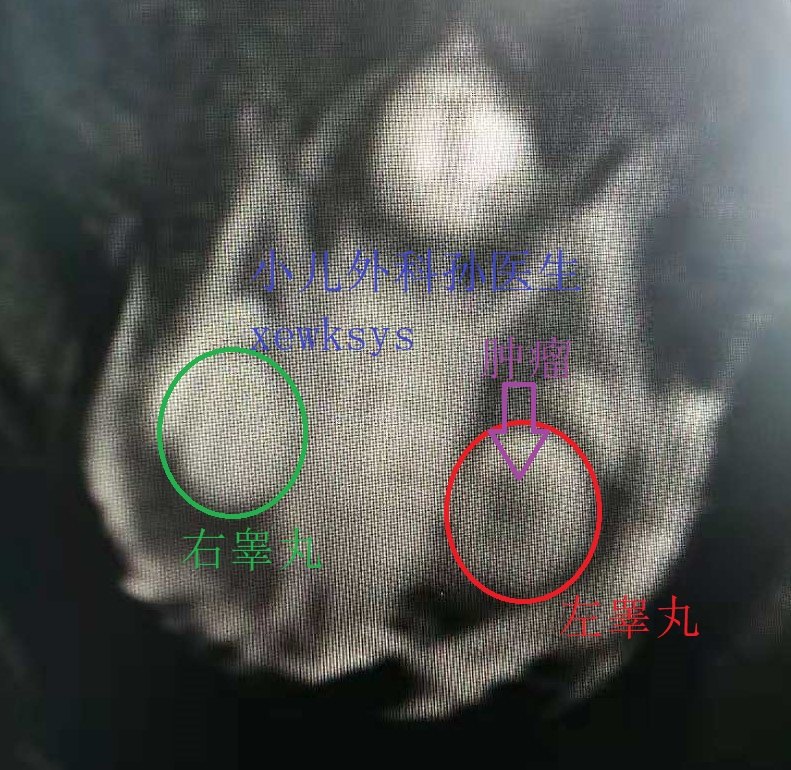

发现睾丸肿瘤以后,医生还可能会给孩子做个磁共振(MR)。

上图:MR左睾丸稍较右侧增大,左睾丸内有一肿瘤